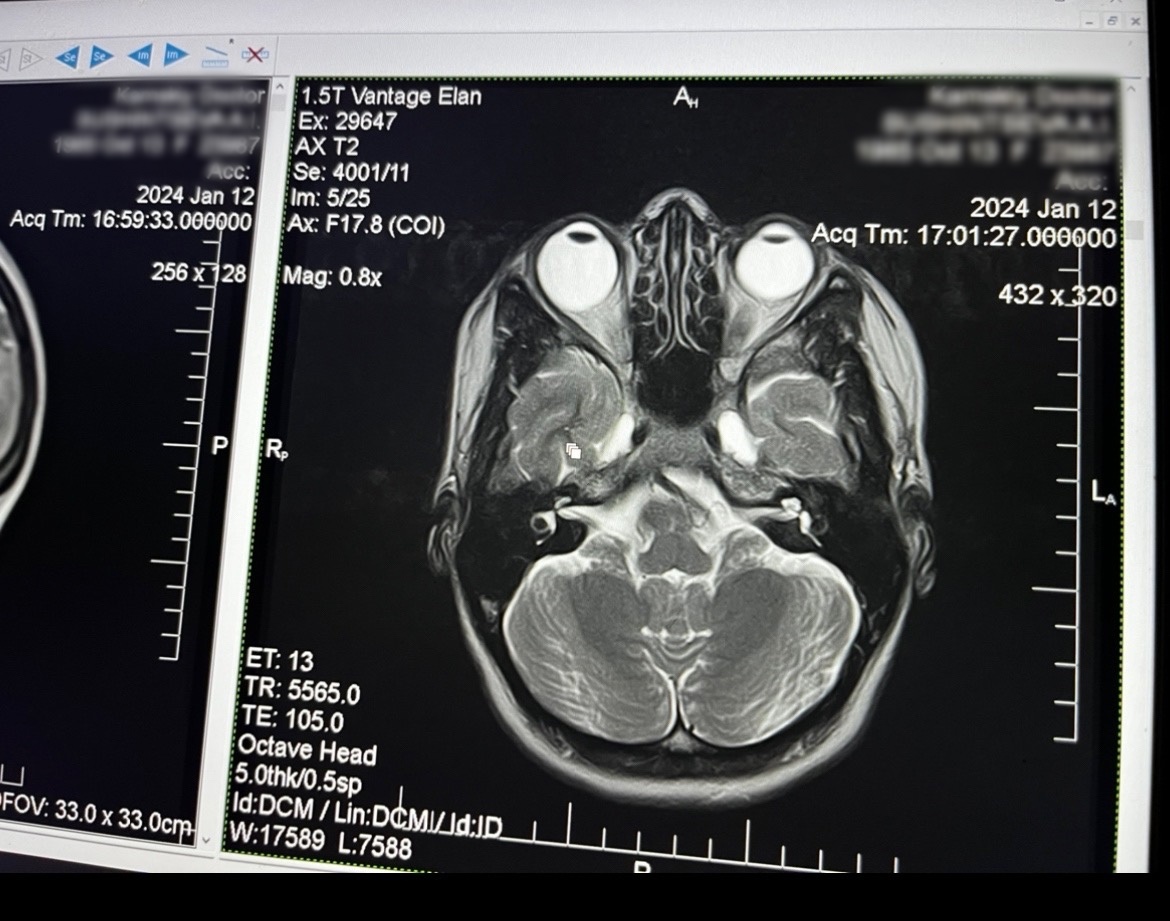

Вот, к примеру, посмотрите на эту картинку:

Рис 3. Авторская иллюстрация (томография мозга)

Это томография девушки с близорукостью на правом глазу в -12 диоптрий а на левом в -4 (для вас её правый глаз находится слева на картинке, а левый справа). Обратите внимание на то, на сколько сильно больше правый глаз относительно левого (ещё раз: в данном случае он слева на картинке). Глаз не растянут. А он на самом деле больше в длину. В нём больше вещества и объёма. Если бы глаз просто сжимался внешними мышцами, то его объём не менялся. Он бы уменьшался в поперечном сечении, но увеличивался в продольном. А тут мы наблюдаем равномерное увеличение глаза по всем направлениям. Вы поняли о чём речь? Если бы глаз на самом деле вытягивался давлением внешних мышц, то он бы становился тоненьким, узким, но длинным. А тут мы видим, что он стал и длиньше и даже немного толще в поперечнике.

И это только первый момент.

Ну ок, вы скажете: да в глазу жидкость, но его можно сжать, я же давлю на него, он вроде как мягкий. Да! Глаз можно сжать. Он мягкий. Вот только если вы его в одном месте сожмёте, он в другом будет более выпуклым. Объём не поменяется. Ели глаз сжать по бокам, он в поперечном сечении станет уже, а в продольном шире (длиньше). Но по томографии разных людей мы уже не раз видели, что глаз близорукого не искажён таким способом. А он вполне равномерно одинаков в своём сечении. Просто он стал больше. И в длину и чуть-чуть в ширину.